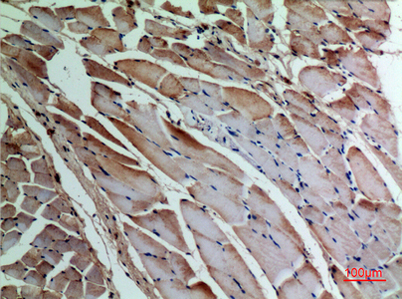

Product name: α-SMA rabbit pAb

Alternative Names: ACTA1; ACTA; Actin, alpha skeletal muscle; Alpha-actin-1; ACTA2; ACTSA; ACTVS; GIG46; Actin, aortic smooth muscle; Alpha-actin-2; Cell growth-inhibiting gene 46 protein; ACTC1; ACTC; Actin, alpha cardiac muscle 1; Alpha-cardiac actinACTA1; ACTA; Actin, alpha skeletal muscle; Alpha-actin-1; ACTA2; ACTSA; ACTVS; GIG46; Actin, aortic smooth muscle; Alpha-actin-2; Cell growth-inhibiting gene 46 protein; ACTC1; ACTC; Actin, alpha cardiac muscle 1; Alpha-cardiac actin

Dilutions: Western Blot: 1/500 - 1/2000. IHC-p: 1:100-300 ELISA: 1/20000. Not yet tested in other applications.

Immunogen: Synthesized peptide derived from the C-terminal region of human α-SMA.

Background: The product encoded by this gene belongs to the actin family of proteins, which are highly conserved proteins that play a role in cell motility, structure and integrity. Alpha, beta and gamma actin isoforms have been identified, with alpha actins being a major constituent of the contractile apparatus, while beta and gamma actins are involved in the regulation of cell motility. This actin is an alpha actin that is found in skeletal muscle. Mutations in this gene cause nemaline myopathy type 3, congenital myopathy with excess of thin myofilaments, congenital myopathy with cores, and congenital myopathy with fiber-type disproportion, diseases that lead to muscle fiber defects. [provided by RefSeq, Jul 2008],